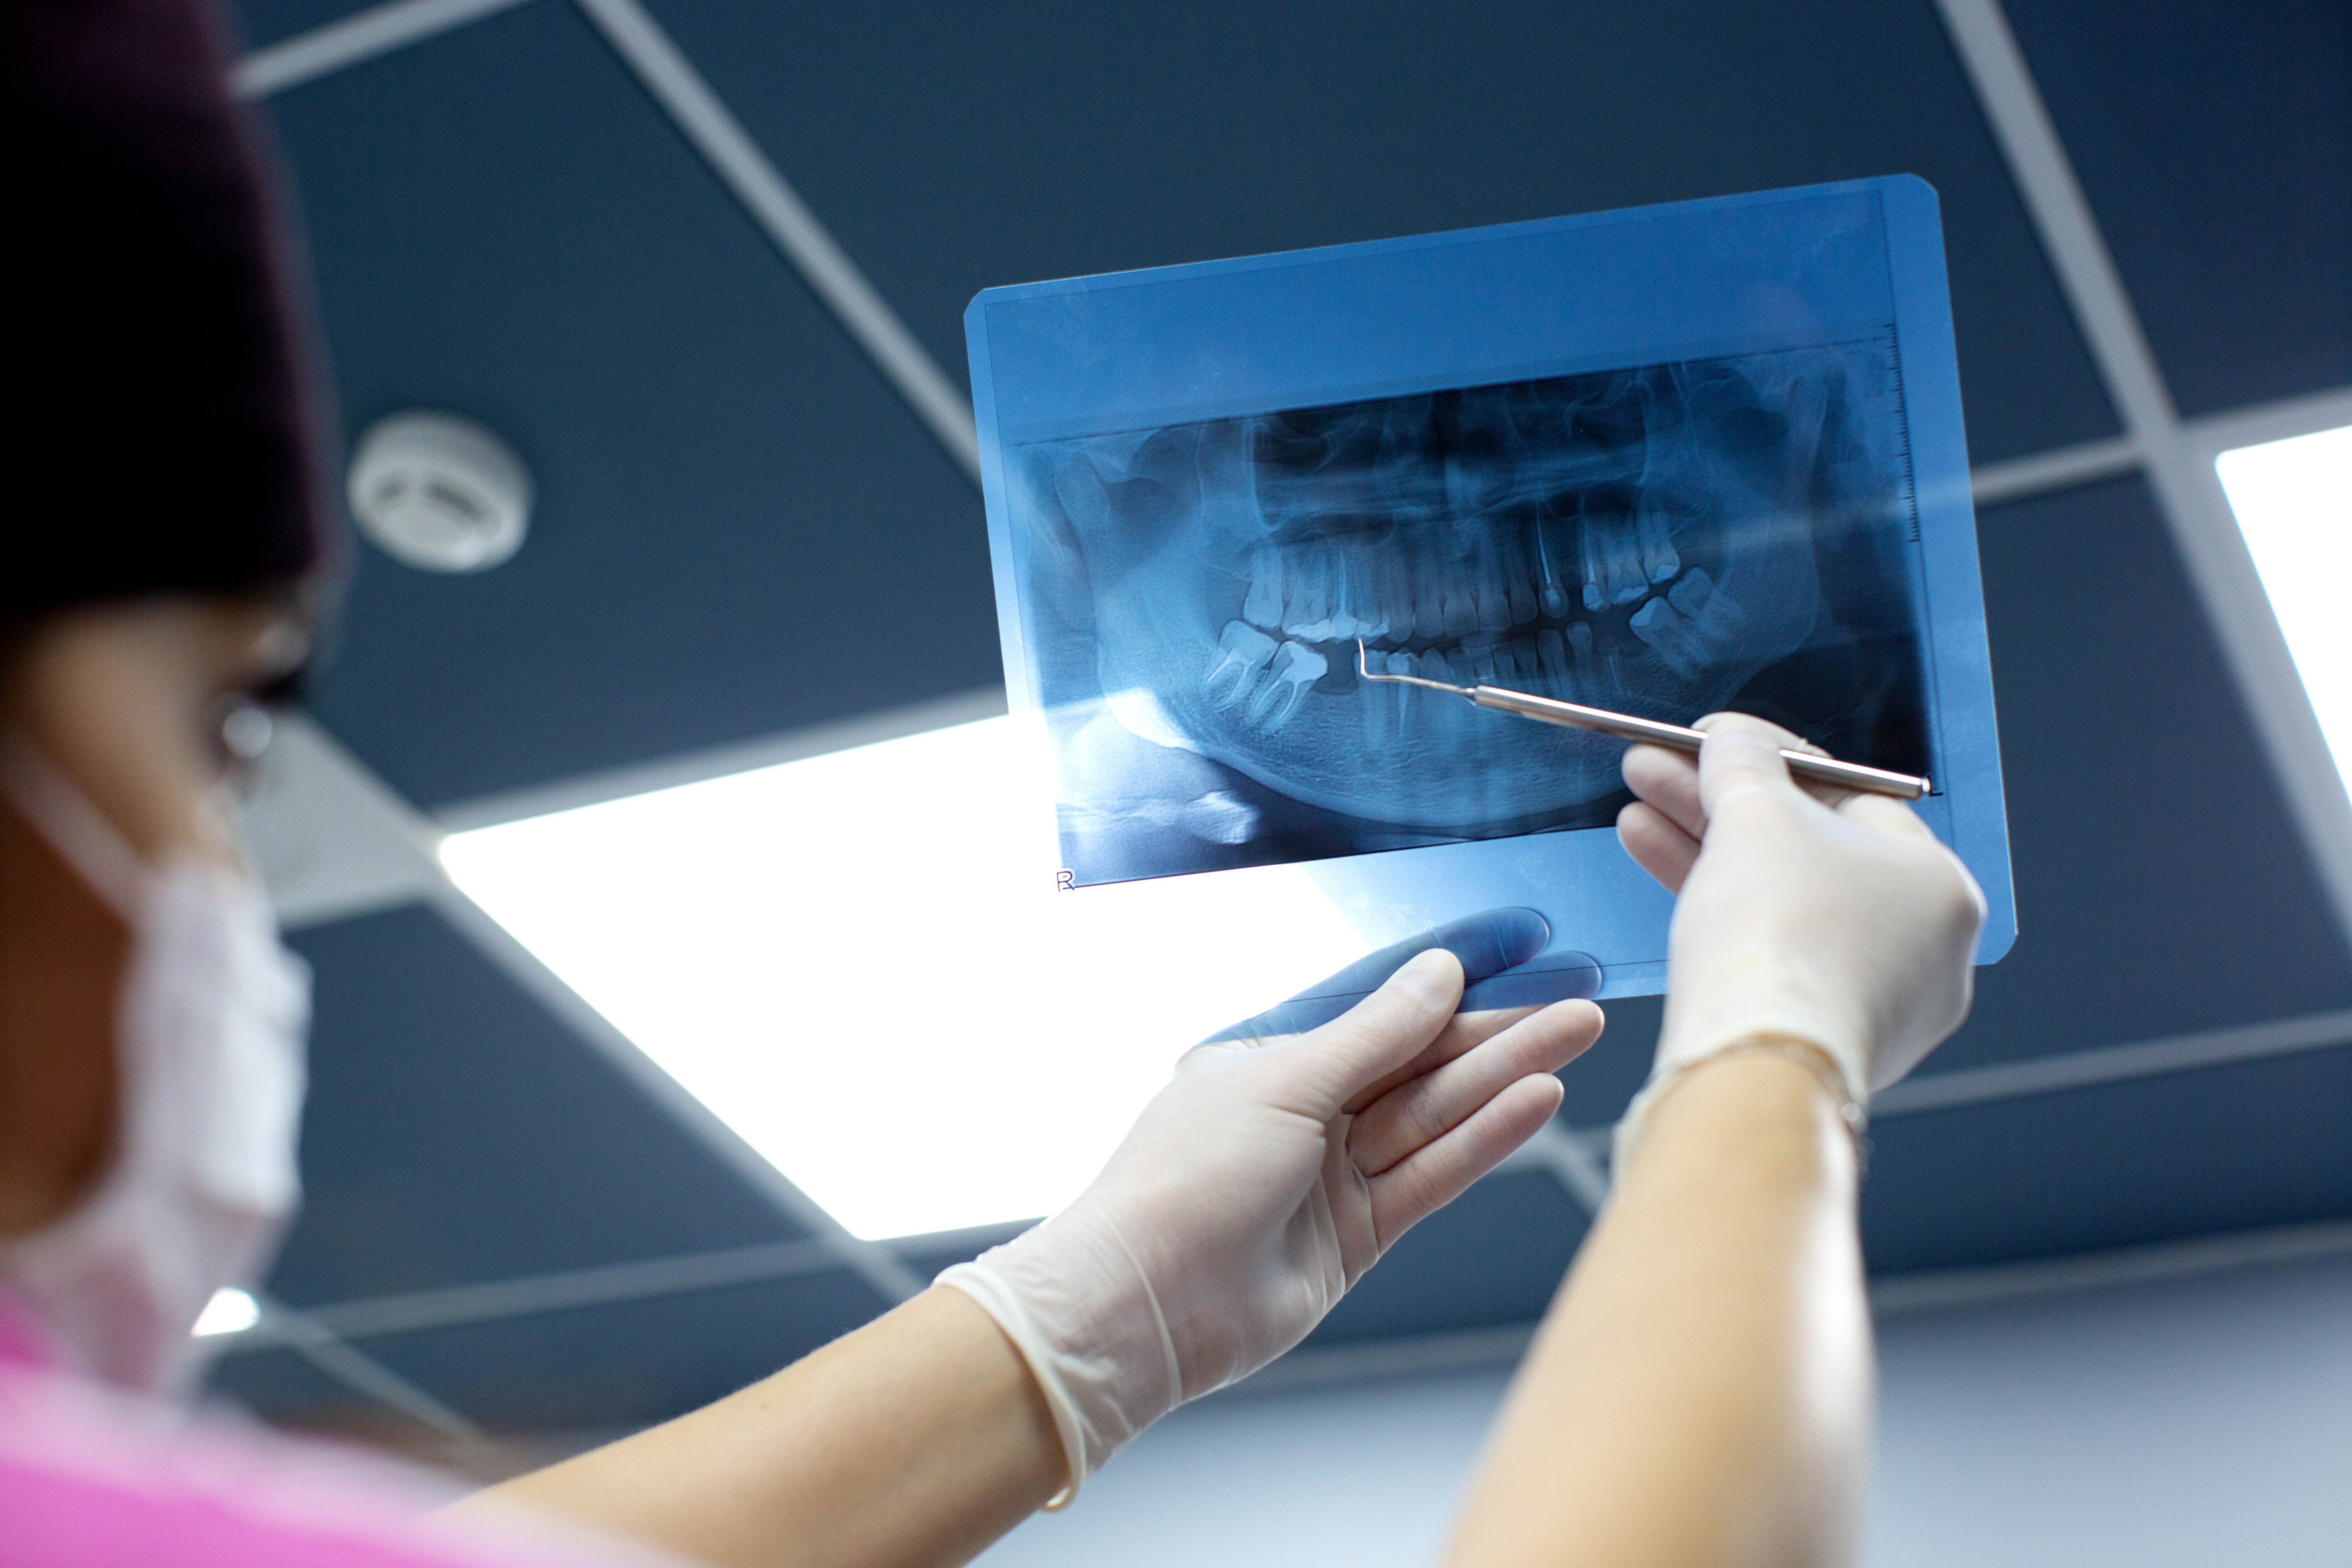

Quick and accurate dental imaging service.

Our X-Ray services provide clear and detailed imaging for accurate diagnosis of dental conditions. With advanced equipment, we ensure safe and precise scans to help our dentists create the best treatment plan for you.